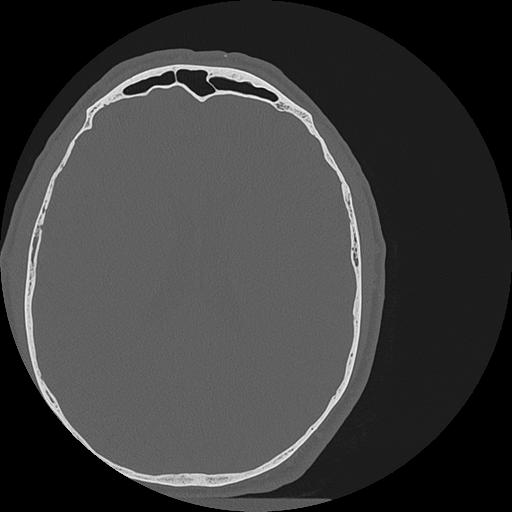

7 HUESO,,Vol,0.5,HUESO,,